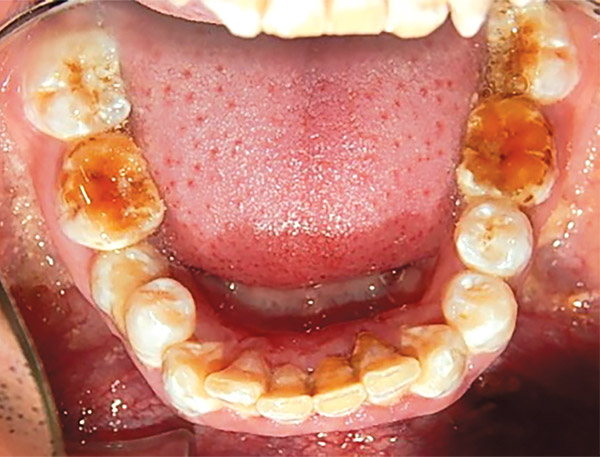

En las fotografías intraorales se muestra la fluorosis dental Tf4 y Tf7, las relaciones molares clase II molar y canina bilateral (Figura 3 y 4), el apiñamiento severo superior e inferior, con el órgano dental 35 en infraoclusión. El overbite aumentado y las líneas medias dentales no son coincidentes (Figura 5), las formas de arco superior e inferior son cuadradas (Figura 6 y 7).

Figura 3. Intraoral derecha.

Figura 4. Izquierda.

Figura 6. Oclusal superior.

Figura 7. Inferior.